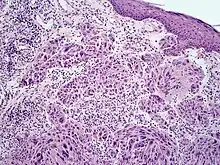

Spitzoid melanoma

Melanoma with features of a Spitz nevus (also known as a "Spitzoid melanoma") is a cutaneous condition characterized histologically with tissue similar to a spitz nevus and with overall symmetry and a dermal nodule of epithelioid melanocytes that do not mature with progressively deeper dermal extension.[1]